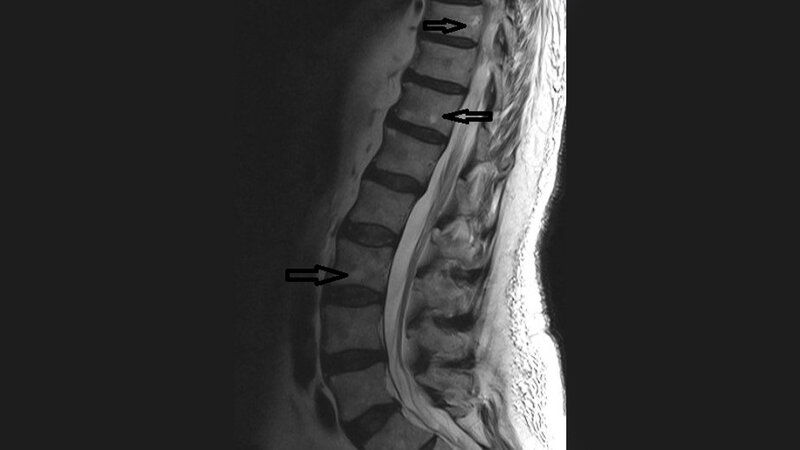

Die meisten Hämangiome sind asymptomatisch. Das kalzifizierende Hämangiom ist eine Variante des Kavernoms. Spinale intramedulläre Kavernome zeigen entweder eine akute zunehmende neurologische Schädigung oder schleichende neurologische Defizite. Die chronisch progressive Myelopathie ist Folge der Hämorrhagie und resultierenden gliotischen Reaktion. Patienten mit intramedullären Kavernomen profitieren weniger von der chirurgischen Therapie als solche mit einer intraduralen extramedullären oder intravertebralen Lokalisation der Läsion.

Most hemangiomas are asymptomatic. Hemangioma calcificans is a variant of cavernous hemangioma with full calcification. Spinal intramedullary cavernomas present either an acute onset of neuro-logical compromise or a slowly progressive neurological decline. Chronic progressive myelopathy occurs due to microhaemorrhages and the resulting gliotic reaction to hemorrhagic products. Patients with intramedullary lesions are more unlikely to improve after surgical resection and derive less of a benefit compared with patients with intradural extramedullary and vertebral hemangiomas.